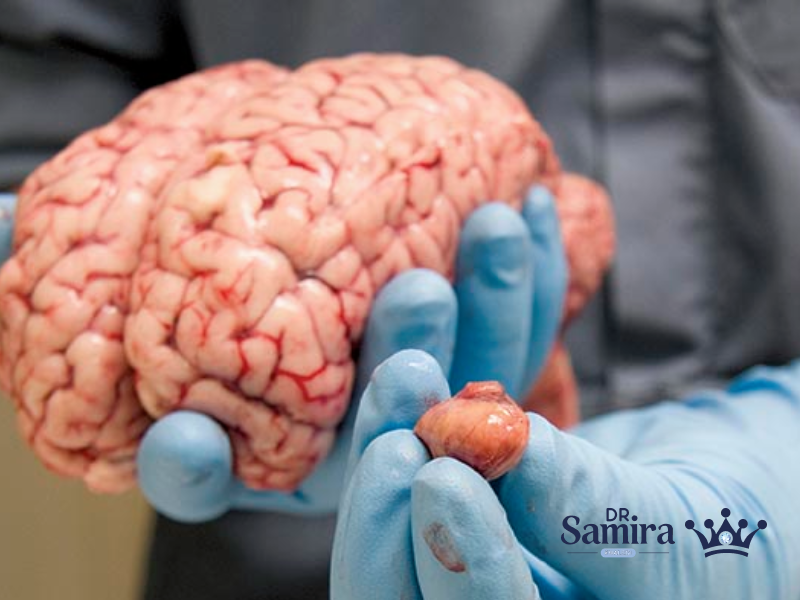

مننژیوم گرید یک یکی از شایع ترین تومورهای مغزی با منشا سلول های مننژ است که...

مننژیوم گرید ۳ یکی از تهاجمی ترین انواع تومورهای مغزی است که تحت عنوان مننژیوم آناپلاستیک...

مننژیوم آتیپیک یا گرید دو (Atypical Meningioma) یکی از انواع تومورهای سیستم عصبی مرکزی است که...